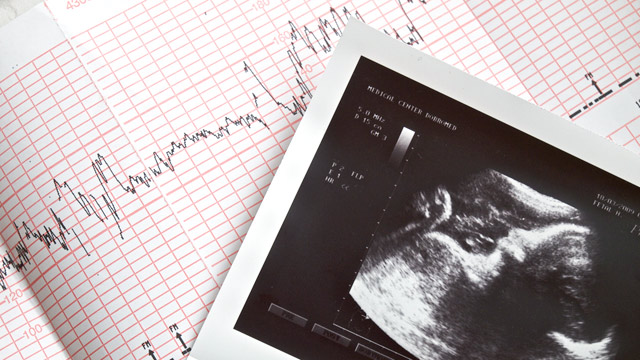

КТГ (кардиотокография): показатели, результаты и расшифровка, нормы

Как устроен кардиотокограф и что он показывает?

Этот прибор включает несколько датчиков:

• Ультразвуковой датчик фиксирует движения сердечных клапанов плода (кардиограмма).

• Тензометрический датчик измеряет тонус матки (токограмма).

• Современные кардиомониторы оснащены пультом с кнопкой, которую нужно нажимать во время шевеления плода. Это помогает оценить характер движений малыша (актограмма).

Данные от этих датчиков передаются в кардиомонитор, где обрабатываются и отображаются на электронном экране в цифровом формате. Также они фиксируются на термобумаге с помощью записывающего устройства. Скорость лентопротяжного механизма варьируется в зависимости от модели фетального кардиомонитора и в среднем составляет от 10 до 30 мм в минуту. Для каждого кардиотокографа предусмотрена специальная термобумага.